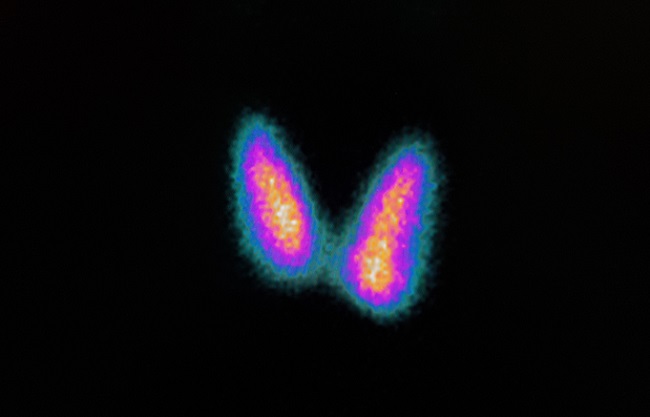

Gambar 2. Gambaran Nodul Tiroid Otonom (Nodul Panas)

- Gambaran NTO adalah aktivitas fokal yang meningkat disertai distribusi minimal hingga tidak tampak aktivitas pada jaringan tiroid sekitarnya

Sidik tiroid adalah satu–satunya pemeriksaan untuk menegakkan diagnosis NTO. NTO sangat jarang bersifat ganas, tetapi sebagian besar menunjukkan sitologi indeterminate. Maka dari itu, bila ditemukan gambaran NTO pada pasien, anjuran FNAB atau reseksi untuk diagnosis definitif dapat dihindari.[6–8]